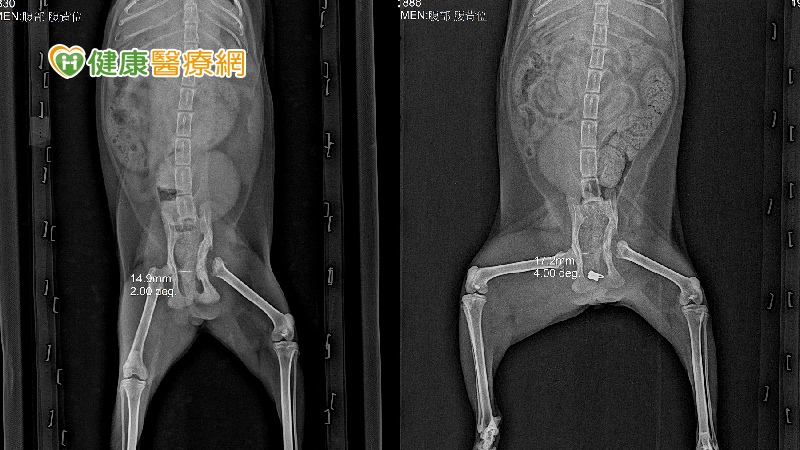

為了解決這個問題,獸醫師黃繼霆首先進行了股骨頭/頸的切除手術(FHNE),待傷口完全癒合後,再處理牠的骨盤腔狹窄問題。參考了相關資料後,決定使用自製的撐開器來增加骨盆腔的寬度。這個撐開器的使用最終使骨盆腔的寬度從原本的14.9mm增加到了17.2mm。

直到5月份,「袞袞」逐漸長大成年體型,但在這段期間,牠的左後腳開始出現跛行問題。經過檢查發現,這是之前骨盆骨折造成的髖關節問題,股骨頭脫出摩擦引起了疼痛,使牠不敢使用這隻腳走路。為了解決這個問題,獸醫師黃繼霆首先進行了股骨頭/頸的切除手術(FHNE),待傷口完全癒合後,再處理牠的骨盤腔狹窄問題。參考了相關資料後,決定使用自製的撐開器來增加骨盆腔的寬度。這個撐開器的使用最終使骨盆腔的寬度從原本的14.9mm增加到了17.2mm。